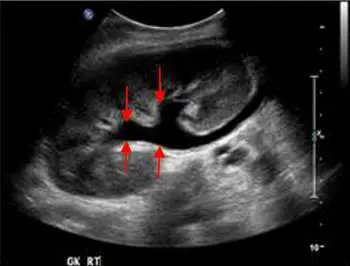

超⾳波掃描如附圖,箭號所指 為何?

圖中標示為「GK RT」(右腎),可見:

- 腎臟整體輪廓尚可辨認,腎皮質回聲相對保留

- 四支紅色箭號分別指向腎臟中央集尿系統區域內多個無回聲(黑色)的液體空間

- 這些無回聲區彼此相通、呈分支狀排列,中央腎盂明顯擴大,腎盞亦同步擴張

- 典型的「熊掌徵(bear's paw sign)」形態——中等至中重度腎盂水腫

- 腎竇脂肪回聲被液體取代,腎盂—腎盞系統界線模糊

- 不見孤立性囊腫(非通連性)、不見腎內出血(出血呈高回聲或混合回聲,非純無回聲)